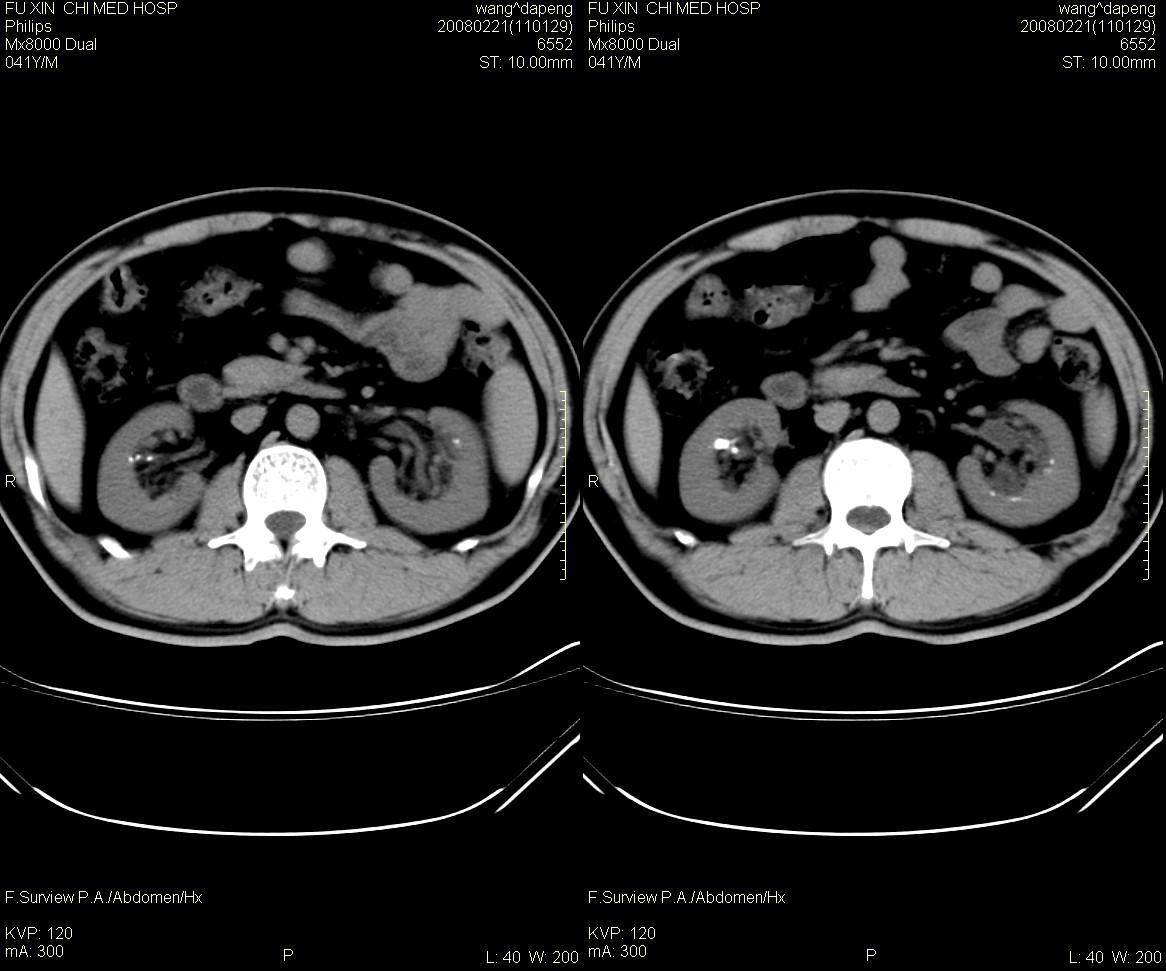

男,41岁,临床发现双肾结石10年。是髓质海绵肾吗?如何确诊。请战友指教。

髓质海绵肾是一种先天性的肾髓质囊性病变, 其特征为肾锥体部乳头管及集合管呈梭形或囊状扩张,并伴发感染和尿路结石形成。在肾标本切面上, 可见髓质中呈海绵状改变。ct平扫表现为肾盏旁锥体内多发小斑点状结石, 成扇形排列.增强扫描后扩张的肾集合管内结石周围有造影剂充盈, 无结石的肾锥体集合管呈条纹状或小囊状造影剂积聚,肾功能正常.

本例支持:髓质海绵肾